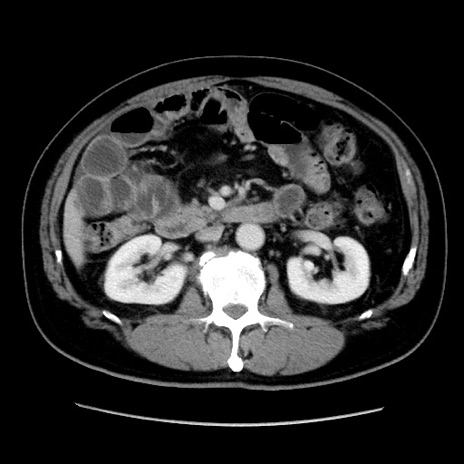

冠状断像

【症例】 70歳代男性

【主訴】 腹痛、嘔吐

【現病歴】 約1ヶ月前より間欠的に腹痛と嘔吐あり、当院消化器内科を受診したところCTで多発する肝臓のLDAを指摘され、精査中であった。以降は消化器症状は安定していたが、2日前より嘔気と腹痛があり、同日より排便・排ガスが消失した。改善認めず、 本日、救急外来を受診した。

【既往歴】 大腸ポリープ切除後。

【身体所見】意識清明・会話良好、BT 36.3℃、BP 127/80mmHg、 P 80bpm、腹部:膨満あり、平坦・軟、上腹部正中および下腹部正中に圧痛あり、反跳痛なし、筋性防御なし。

【データ】WBC 7200、CRP 0.77